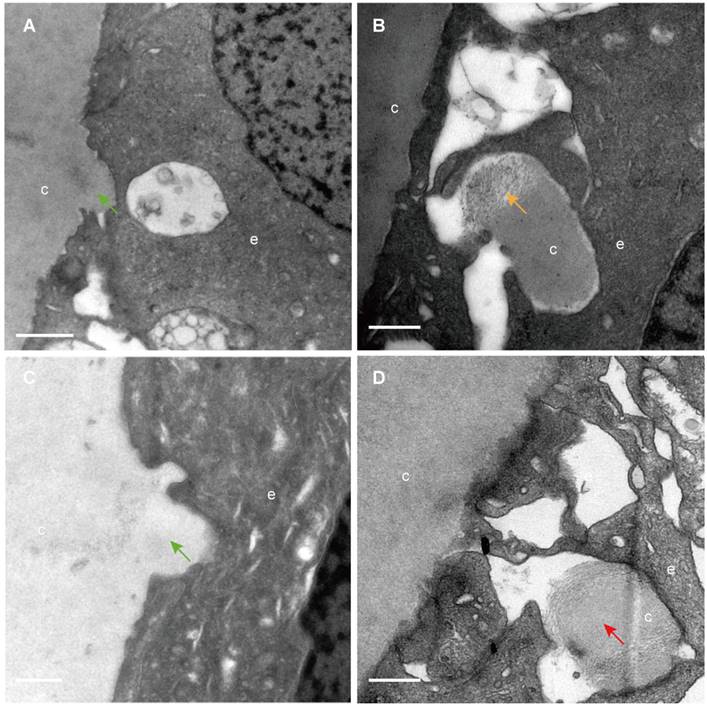

The classical EM study reported that the lens capsule is a uniform and non-cellular structure composed of electron-dense materials, which smoothly covers anterior surfaces of the HLECs [10-13]. Interestingly, our results showed that in some cases human lens capsule is not as smooth as reported before. We analysed 12 donated lenses and 12 aLCs of cataract patients obtained from routine cataract surgery ultrastructurally (Table 1), and found that the capsules from 3 (25%) donor lenses and 2 (17%) cataract patients could protrude into the epithelial cells in some unidentified regions but not in the equatorial zone (Figure 1). The protruding capsules appeared to display three different morphological characteristics, with representative TEM images of one donor lens of a 51-year-old shown in Figure 1. Different colours arrow shows different morphology of the protruding capsule. Figure 1A, B illustrates the capsule protruding into the epithelial cells (green arrow). Figure 1C, D shows the protruding capsule completely enclosed by the epithelial processes and had become loose on the periphery (red arrow). Figure 1E, F exhibits the filament-like changes (orange arrow) of the embedded capsule tissue. These three different morphological capsule protrusions were observed in the human lenses of some ages. The detailed information is presented in Table 1. Representative images of the protruding capsule of different ages are shown in Figure 2. The colors of the arrows signify specific features of the protrusions.

Different capsule protrusion morphology in a donor lens. The capsule protrudes into HLECs (A, B green arrow). The protruding capsule is completely enclosed by the epithelial process and is loose on the periphery (C, D red arrow). The filament-like changes of embedded capsule tissue (E, F, orange arrow). Scale bars: A = 1 µm, B = 0.5 µm, C-F = 0.2 µm. All TEM images are from a 51-year-old donor.

Capsule protrusions in human lenses of different ages. Initial capsule protrusions (A, C green arrow), enclosed capsule (D, red arrow) and filament-like capsule protrusions (C, orange arrow) was observed in different ages of human lenses. Different colours arrow shows different morphology of the protruding capsule. The representative images of the capsule were obtained from a 41-year-old donor (A), a 51-years-old donor (B), a 65-year-old patient with cataract (C) and a 67-year-old donor (D). Scale bars: A = 1 µm, B-D = 0.5 µm.

We found that the capsule protruded into the epithelium in some areas and the capsule components might be involved in potential processing. Previous studies reported the lens capsule to be a non-cellular, smooth, and transparent basement membrane secreted by HLECs and covering the surface of HLECs [10-13]. However, our results showed that the human lens capsule is not smooth in some regions. Furthermore, some protruding capsules appeared as loose filament-like components with electron lucency, which might indicate phagocytosis by the epithelial cells. Such a process was found in the lens of donors aged 41, 51 and 67 years and in cataract patients aged 65 and 79 years, but not in the lens of other donors of similar age, and did not appear in the young donors or young cataract patients in the current study. It appears no obvious trends were found in the capsule protrusions in different ages of human lens and more researches are needed. These results contradict those of previous studies showing the capsule to be smooth and composed of uniformly electron-dense materials [14, 15]. This specific morphological feature of the capsule in the present study might represent the progressive degradation of the protruding lens capsule, or there might be a form of communication between the capsule and epithelial cells. Many epithelia have the potential to transform into non-professional phagocytes and engulf and degrade material; for example, shedding photoreceptor outer segments are phagocytosed by retinal pigment epithelial cells to prevent debris accumulation and thereby maintain tissue homeostasis [16, 17]. The question is raised whether the lens epithelial cells have the same potential of transforming into non-professional phagocytes like other epithelia. Further studies are needed to determine this.